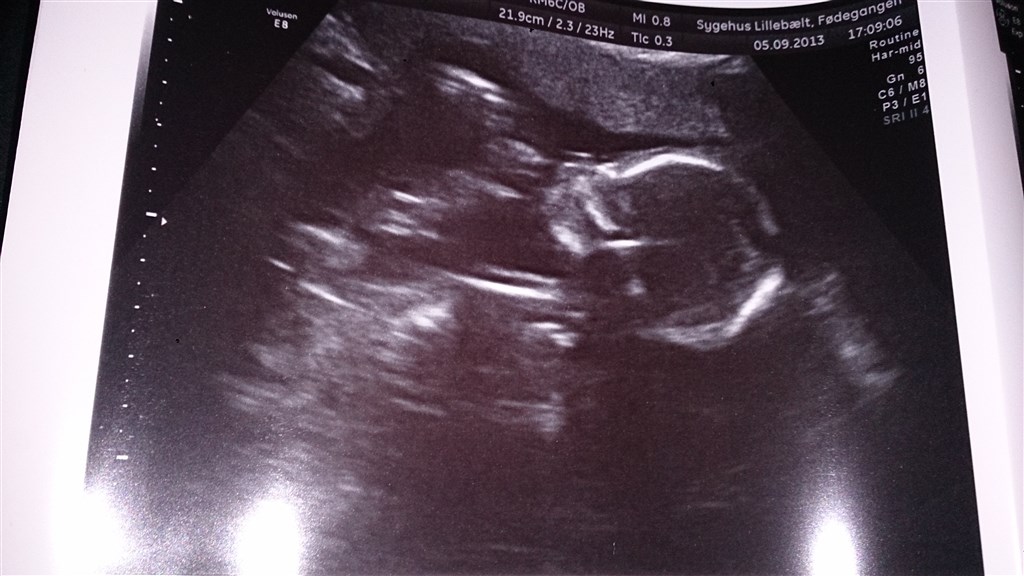

Wee så var vi til MD scanning idag, vi venter os en sund og rask lille dreng, der var ski godt gang i ham, han slog en kolbøtte da scanningsdamen skulle scanne hjertet, men nej hvor jeg glæder mig til han kommer ud

Lige et lille glædes indlæg fra mig og et lille billede af bassemanden